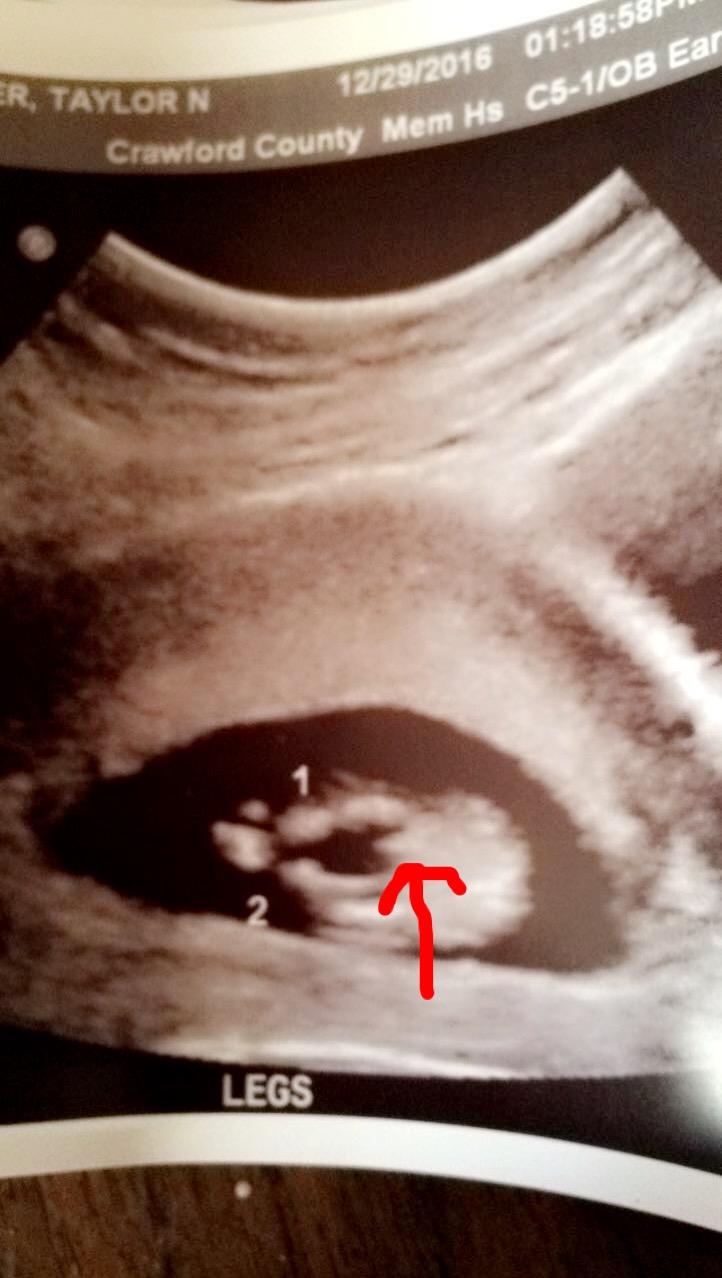

Boy from me :)

Boy!

boy

I thought 13 weeks was too early for potty shots?